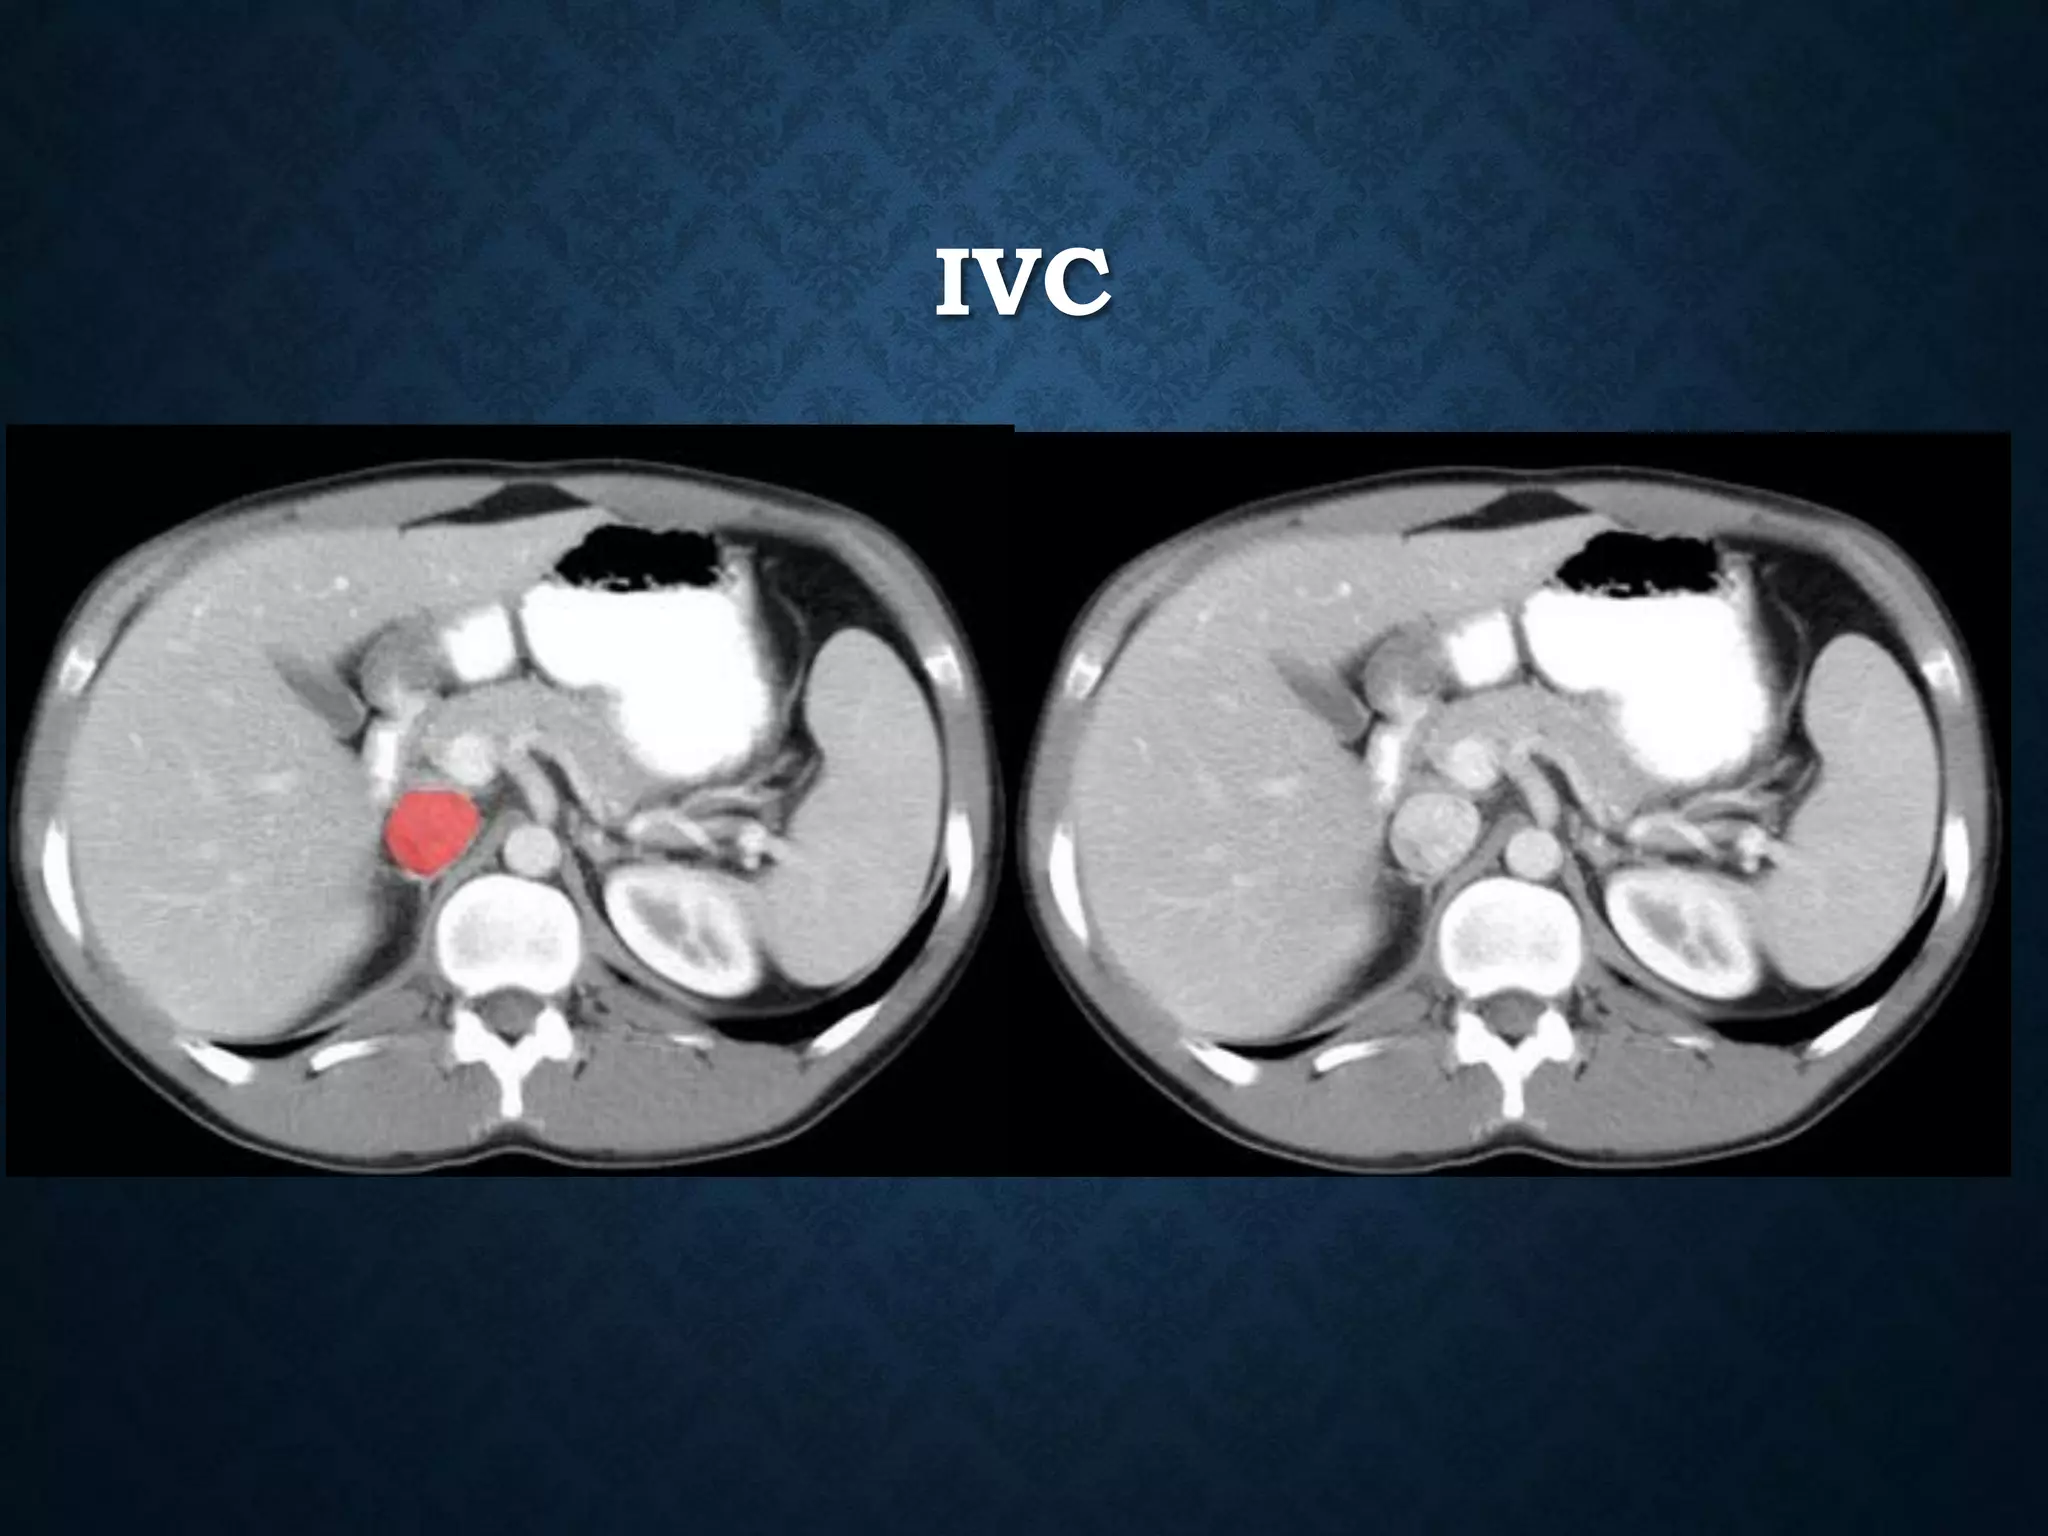

IVC